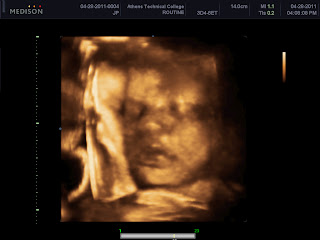

A few weeks ago a friend of mine posted on facebook that the sonography department at Athens Tech needed volunteers for 3D ultrasounds.  I have always wanted to do a 3D ultrasound, so I jumped at the chance.  Sam and I were absolutely amazed at what we were able to see.  Annabelle currently weighs 4lbs 5 oz.  She is on track to be somewhere between 7 and 8 pounds.  Yay!  It looks like Tyler will be the big baby of the family.